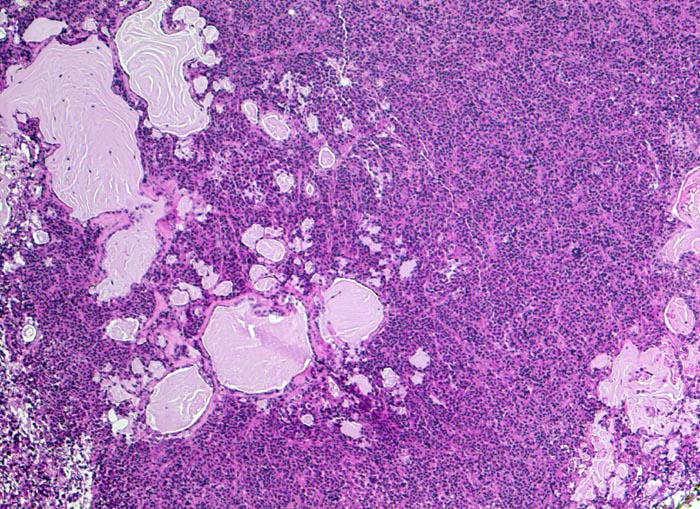

Prolaktinom

Hypophyse, Vorderlappen